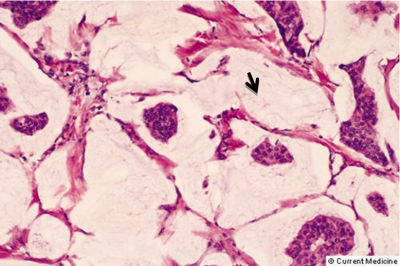

ה- DCIS היא השאת הממארת הכי מוקדמת שניתן לגלות כיום. היא מתאפיינת בהיותה מחלה מקומית של השד אשר נדיר כי מערבת בלוטות או שולחת גרורות. לכן הטיפול במחלה זו הוא מקומי. במידה והנגע הזה נשאר, כ-30% יפתחו את הצורה התוקפנית יותר של סרטן השד והיא ה- Invasive carcinoma (IC). בנגעים אלה, מתפתחות קבוצות (קלון) של תאים בעלי יכולת לפרוץ מחוץ לצינורית החלב אל השומן מסביב ולשרוד שם (תמונה 31.12 -33.12).

תאים אלה יכולים לנדוד גם לבלוטות הלימפה או להיהפך לגרורות באיברים אחרים. למעשה, המעבר מ-DCIS ל-IC הוא מעבר ממחלה מקומית למחלה אזורית-מערכתית. ב-70% מהחולות המאובחנות בשלבים מוקדמים (Stage I, II) המחלה היא מקומית-איזורית, ואילו ל-30% יש מחלה מערכתית. החלוקה של סוגי השאתות השונות לפולשנית/ לא פולשנית והדרגה מוצגת בגרף 7.12: